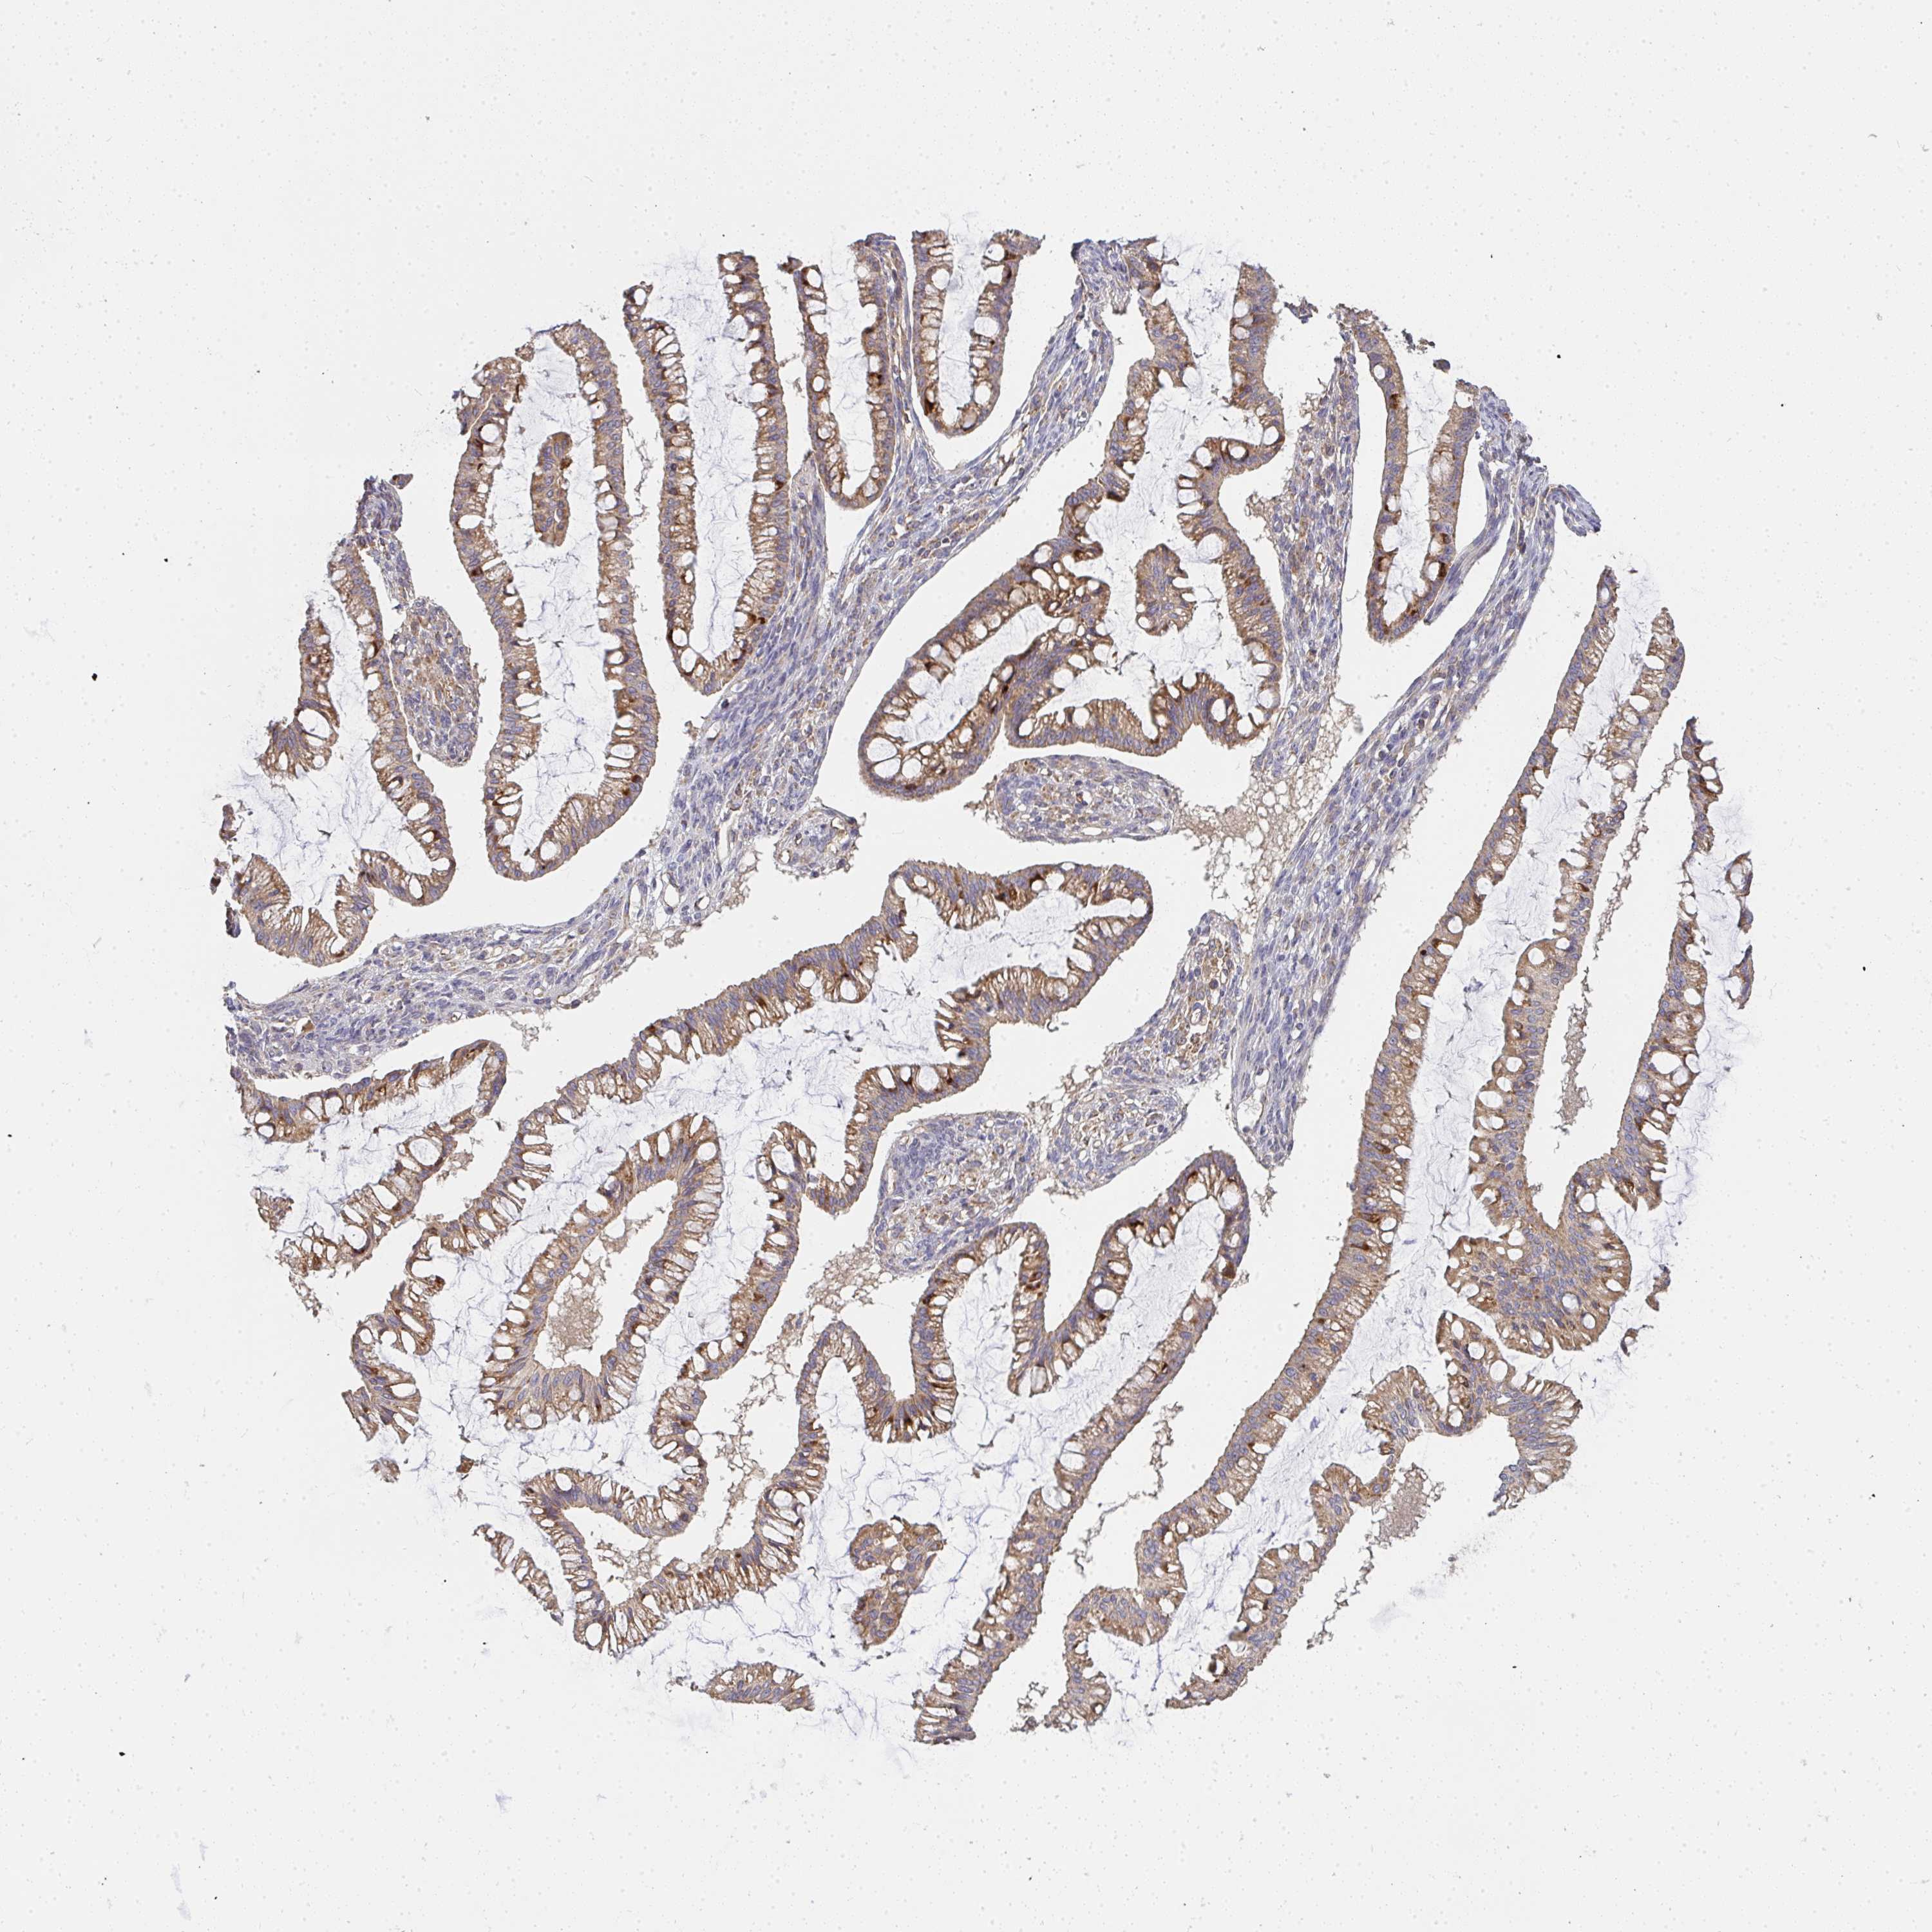

OVARIAN CANCER - Protein expressioni

A mouse-over function shows sample information and annotation data. Click on an image to view it in a full screen mode. Samples can be filtered based on level of antibody staining by selecting one or several of the following categories: high, medium, low and not detected. The assay and annotation is described here.

Note that samples used for immunohistochemistry by the Human Protein Atlas do not correspond to samples in the TCGA dataset.

Antibody stainingi

Antibody staining in the annotated cell types in the current human tissue is reported as not detected, low, medium, or high, based on conventional immunohistochemistry profiling in selected tissues. This score is based on the combination of the staining intensity and fraction of stained cells.

Each image is clickable and will lead to virtual microscopy that enables deeper exploration of all samples and also displays staining intensity scores, fraction scores and subcellular localization as well as patient and tissue information for each sample.

Antibody HPA058284

Antibody CAB020701

Cystadenocarcinoma, mucinous, NOS